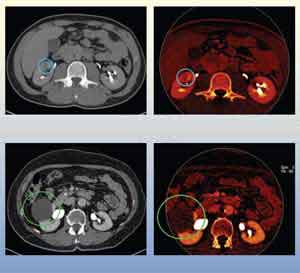

• Images from two dual-energy CT urogram cases

Soft Tissue Removal

Because cysts and masses can have similar attenuation characteristics, it can be difficult to discern the lesion type. Dual energy CT can be used to distinguish cysts from masses because cysts do not absorb iodine. These images are from two dual-energy CT urogram cases. From the iodine enhanced scans (Left, top and bottom), images containing only iodine signal can be created (Right, top and bottom). Cysts will appear black in these images, indicating a lack of blood flow to the area (Right, bottom). A mass, which was a Grade 3 renal cell carcinoma, appears red like the other iodine-enhanced regions (Right, top).